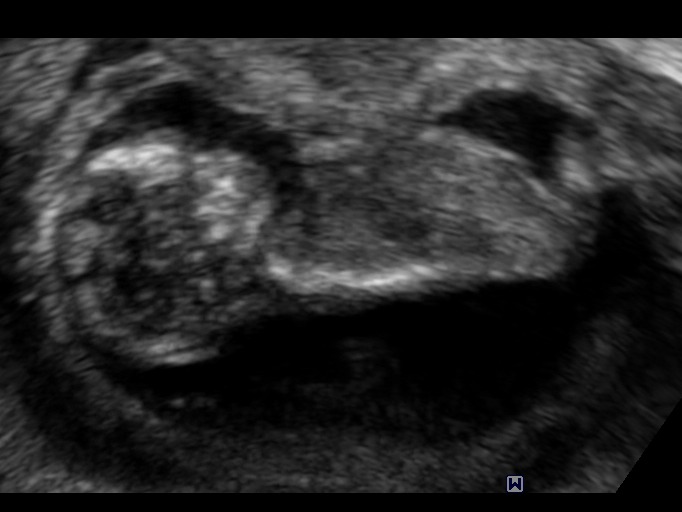

13 weeks...is this a girl most likely? Or boy?

I'm new here and was wondering if anyone would be able to guess whether this is most likely going to be a girl/boy. These were taken at an elective ultrasound place at 13 weeks 4 days and the tech was saying girl throughout most of the scan but then said thought these looked boy?? So she was undecided. What do you ladies think? I feel like the first picture may look like a boy at first but looking closer maybe girl parts? I'm just trying to get an idea of whether or not to expect pink/blue soon! Attachment 24921